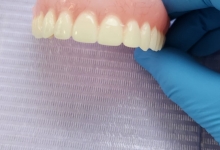

SUPRAPROTEZAREA PE IMPLANT